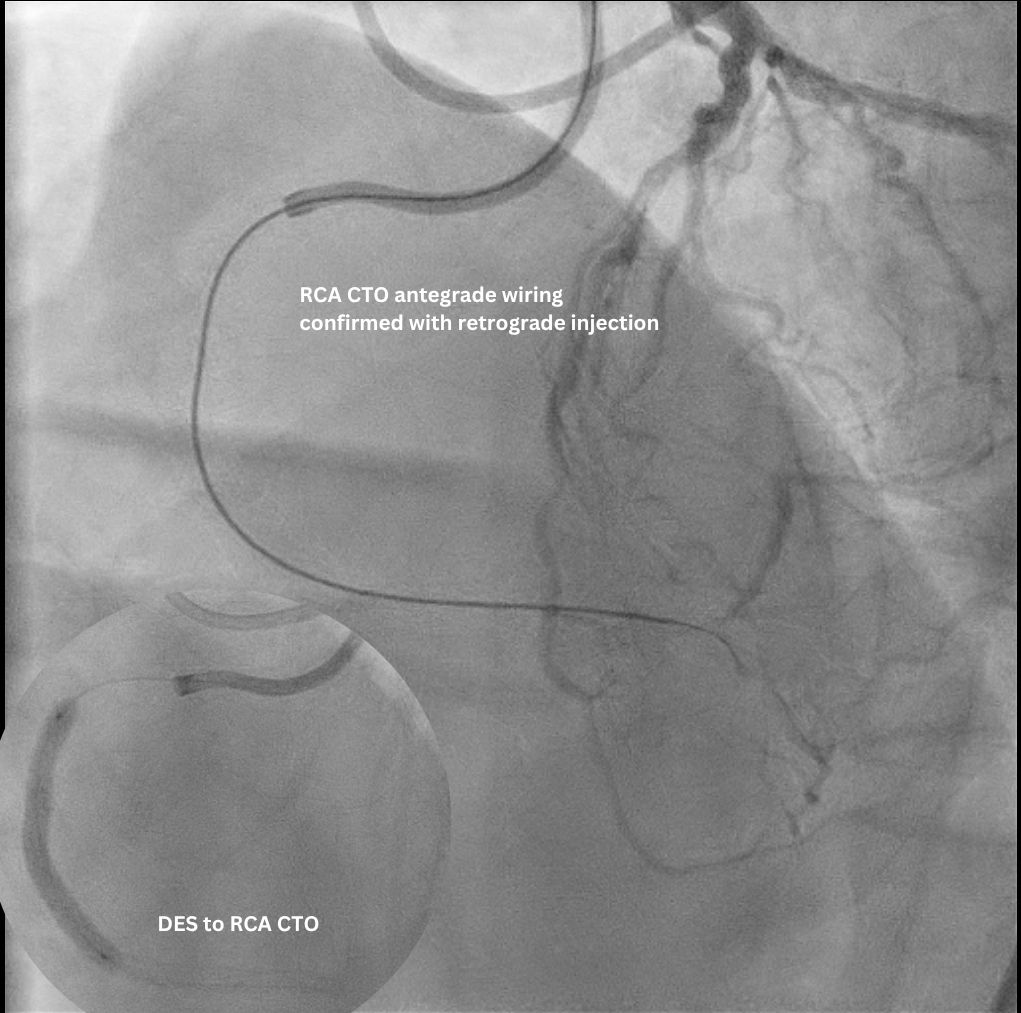

The staged PCI for the RCA CTO was completed uneventfully via an antegrade approach. Subsequent LCA angiogram showed a p-d LCx CTO supplied by an ipsilateral collateral from the D1/ LAD via an epicardial channel. RCA angiography confirmed no interventional contralateral supply. Detailed lesion analysis showed an ambiguous proximal cap (with the atrial branch as a large side branch), ~20 mm CTO length, a bend > 45¡Æ, and the distal cap located precisely at the dLCx/OM2 bifurcation.

Access was achieved via RRA and US-guided RFA puncture. A 7F SBP 3.5 guide was engaged to LM, and a 6F IL 3.5 guide was in oRCA, confirming no contralateral supply to LCx CTO. After a failed antegrade IVUS guided puncture by GW Gaia Next 2, the strategy shifted retrograde. GW Sion supported by microcatheter Caravel successfully navigated D1 across LAD stent struts, visualizing the ipsilateral epicardial collateral to OM2. The wire was exchanged to SUOH 03 and then advanced to OM2. After initial retrograde wiring failures by a UB3, a Gladius MG successfully crossed the CTO body to pLCx. IVUS to pLCx confirmed retrograde wire in subintimal plane. Multiple attempts R-CART failed in p-mLCx despite wire escalation to GW Gaia Next 3. Repeat IVUS showed enlarging pLCx hematoma, necessitating deployment of a DES (ULTIMASTER NAGOMI 3.0 mm/18 mm) to seal the entry point. Successful stent based R-CART was then achieved with Gaia Next 3, confirmed by IVUS. The IL 3.5 guide was moved to LM as an antegrade Ping-Pong guide for RG3 externalization after successfully advancing retrograde wire and microcatheter to the IL guide. The m-dLCx was prepared by SC balloons and a DES (ULTIMASTER NAGOMI 2.5 mm/50 mm) was deployed to the p-dLCx-OM2, overlapping the proximal DES. A D1 perforation was noted and then successfully treated with fat embolism via the retrograde microcatheter. Final angiogram and IVUS confirmed optimal results.